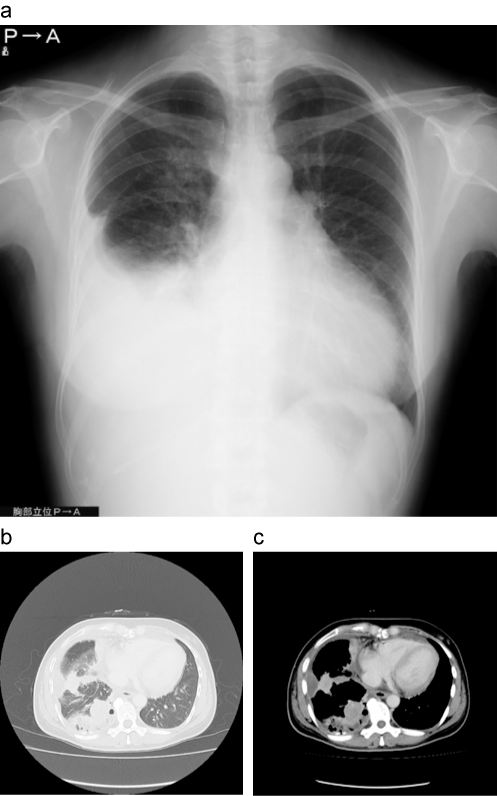

癌性胸膜炎症例

a:胸部単純X線

b:胸部CT(肺野条件)

c:胸部造影CT(縦隔条件)

単純X線画像(a)では右胸水が中等量貯留しており、肺野に明らかな異常陰影は認めない。胸水排液後のCTにて、右下葉に腫瘤影を認める(b、c)。